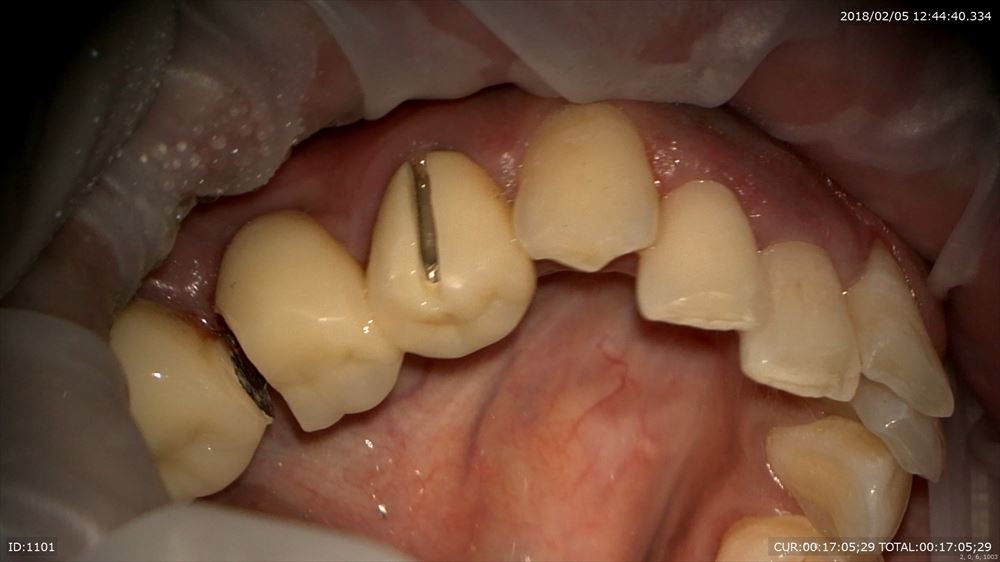

今日が2回目イスムスの整理や根管形成の終盤。

うん。感染をしっかり色で分けて確認

確実に。マイクロエキスカ

イスムスに感染これはマイクロスコープでしか見えません。

こんな状態から 右 ここまで2回 左 次回終了。